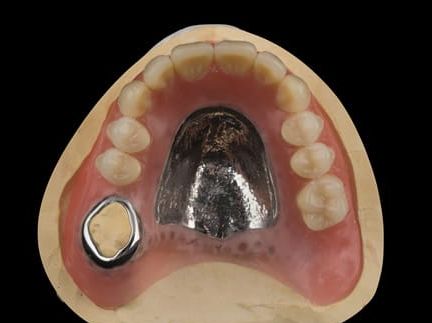

- Cobalt chromium reinforced gasket denture - using a Molloplast B "O" ring to retain and stabilise the denture. This was my professional preference as this was the least invasive and simplest solution to this dental problem. Should the UR7 require removal in the future - an artificial tooth could be added - resulting in a complete denture. The patient would have adapted to the denture fully by this stage and have good neuromuscular control of the prosthesis.

Following consultation and second discussion appointment the patient chose to have option 2 namely, a window denture - maxillary cobalt chromium based partial denture. The clinical situation and treatment process is shown in detail below with photographs. The patient was successfully rehabilitated with this and her quality of life considerably improved. The clinical work was provided by Finlay and the technical work by Rowan.